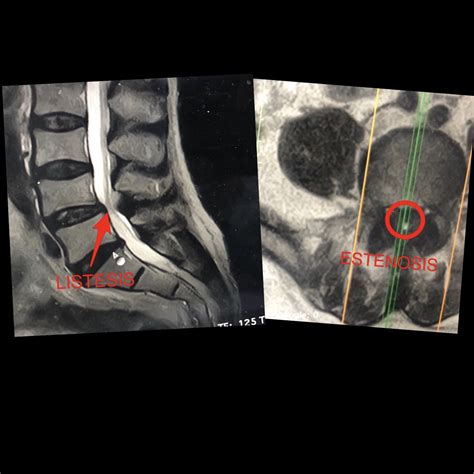

Operación De Estenosis De Canal Lumbar, Operación de estenosis de canal lumbar en L4L5, 960.94 kB, 00:41, 13,779, ICAC Cirugía Avanzada de Columna, 2021-08-06T10:23:21.000000Z, 3, Hernia Discal Lumbar: operación y estenosis de canal - YouTube, www.youtube.com, 1280 x 720, jpeg, WebLa operación consiste en una ampliación del canal espinal para descomprimir los nervios. Es una operación muy segura, y su duración no suele ser superior a una hora.. WebTratamiento de la estenosis raquídea lumbar. Video de la estenosis raquídea lumbar. Como la laminectomía, el objetivo de estas opciones quirúrgicas es descomprimir, ya. WebLa cirugía avanzada de estenosis de canal es una intervención de apenas 90 minutos, lo cual permite operar a personas mayores o muy delicadas para quienes la anestesia es., 20, operacion-de-estenosis-de-canal-lumbar, Novedades y Muebles WebLa operación consiste en una ampliación del canal espinal para descomprimir los nervios. Es una operación muy segura, y su duración no suele ser superior a una hora.. WebTratamiento de la estenosis raquídea lumbar. Video de la estenosis raquídea lumbar. Como la laminectomía, el objetivo de estas opciones quirúrgicas es descomprimir, ya. WebLa cirugía avanzada de estenosis de canal es una intervención de apenas 90 minutos, lo cual permite operar a personas mayores o muy delicadas para quienes la anestesia es.

WebEl procedimiento quirúrgico que se realiza más a menudo para la estenosis de columna lumbar es la laminectomía descompresiva, a veces acompañada de una fusión espinal..

WebLa cirugía de la estenosis de canal esta indicada en pacientes que presentan una estenosis de dicho canal junto con síntomas propios de la compresión nerviosa, y. WebEl tratamiento de la estenosis del canal lumbar está cambiando radicalmente. Se tiende a la cirugía mínimamente invasiva , es decir, pequeñas. WebLa cirugía que se realiza para tratar la estenosis espinal se llama cirugía de descompresión espinal. El objetivo principal de la cirugía es liberar espacio en la. WebObjetivo: Determinar los efectos de la rehabilitación activa despues de una cirugía por canal lumbar estrecho cuando se compara con “cuidados post-operatorios. WebAnimación realizada por Javi Arán.Voz en off: Vere ÁlvarezDr. Bernardo Mosqueira CenturionLes recordamos que pueden seguirnos en nuestra web y redes sociales...

WebLa operación más frecuente es una simple descompresión. Esta intervención consiste en retirar la pared posterior del canal con el fin de ensanchar el conducto vertebral. WebLa lesión de los músculos en la intervención deben seguir un proceso de reparación. Dependiendo del tipo de cirugía, si ha sido con una apertura grande o con microcirugía,. WebLa estenosis lumbar es un estrechamiento del canal raquídeo a expensas de una proliferación ósea que comprime las estructuras nerviosas que contiene. Los.